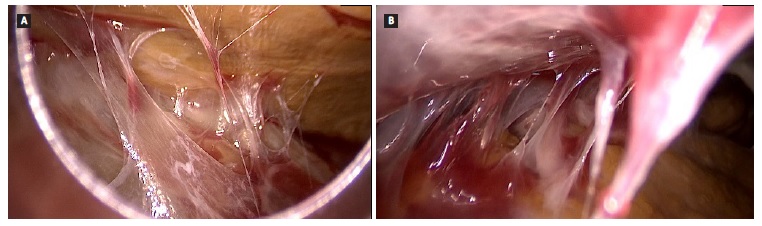

Patient has been admitted to the emergency department in distress with abdominal tenderness, nausea, vomiting, fever, and a cloudy peritoneal effluent (PE). Laboratory studies revealed hemoglobina 12.5 g/dL, C-reactive protein 1 mg/dL and an exudative PE with 5900 leukocytes/μL with 100% polymorphonuclear cells. A bacterial peritonitis diagnosis was assumed, and intraperitoneal vancomycin and ceftazidime were prescribed. Because of rapid deterioration, she was admitted to the Intensive Care Unit. After hemodynamic stabilization, she was transferred to the Nephrology department 48 hours after. The patient was diagnosed with methicillin-sensible Staphylococcus aureus (MSSA) peritonitis. The peritoneal catheter was removed 3 days after admission and the patient switched renal replacement therapy to hemodialysis (HD). Contrastenhanced abdominal computed tomography (CT) scan revealed parietal calcifications, with bowel thickening, but without bowel dilatation or signs of intraperitoneal exudates (Fig. 1).